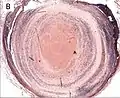

Thrombus showing circumferential lines of Zahn.